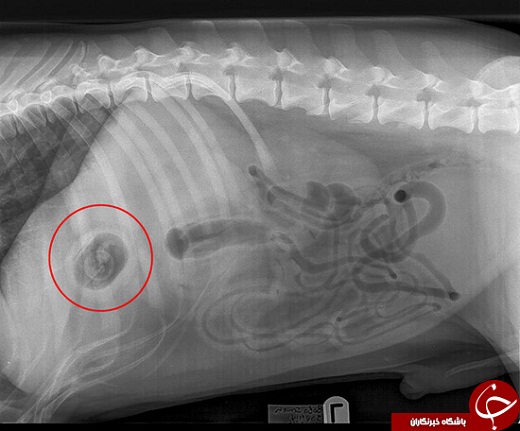

معاینات اولیه هیچ سر نخی به پزشکان نداد اما پس از عکس برداری ایکس مشخص شد که چرا این سگ نمیتواند غذا بخورد.

دامپزشکان

با بررسی عکسهای بوبو مشاهده کردند که شیء کوچکی در روده این سگ وجود

دارد و بلافاصله تصمیم گرفتند که عمل جراحی انجام دهند.